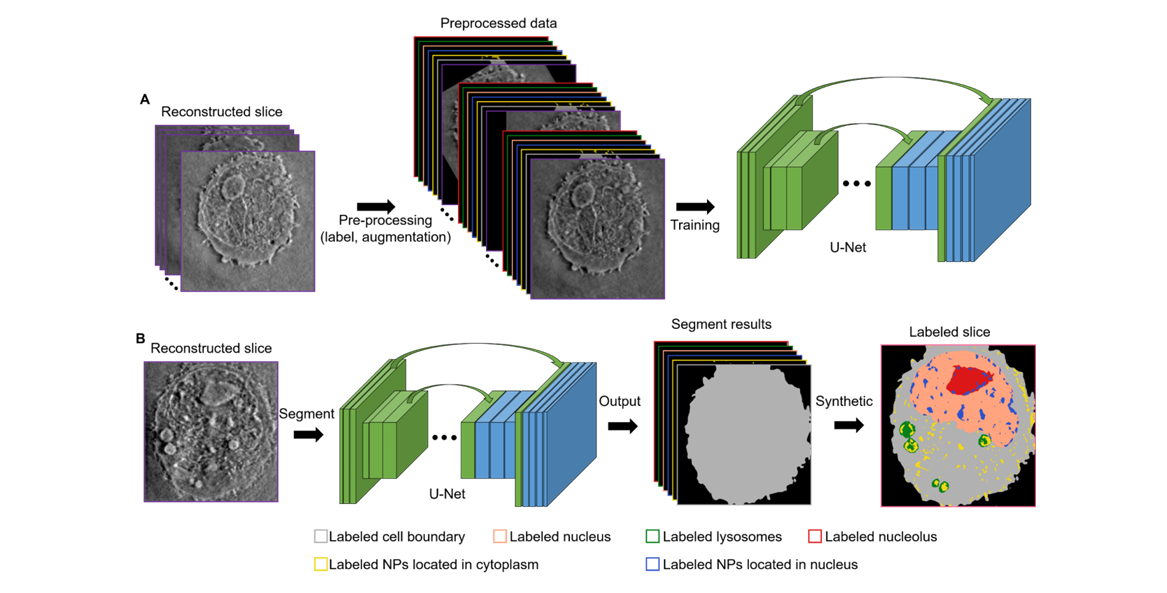

这项研究里弄出来的 DL-HXT 技术就把这些难题解决了。它可聪明了,能自己自动地找到

细胞本身的结构,像细胞核啥的,还能找到细胞里的纳米小颗粒。而且不管是细胞结构还是纳米小

颗粒,它都能自动地、按照统一标准把它们区分开、认出来,还能做统计分析呢。

数据分析与结果解读

图像分割与识别:利用 DL - HXT 技术自带的图像处理软件或其他专业的图像分析软件,对采集到的图像进行分割和识别。将纳米颗粒和细胞器从复杂的细胞图像中分离出来,标记出它们的位置和边界,以便进行定量分析。

(1)改进分割算法,使得分割的效果更好